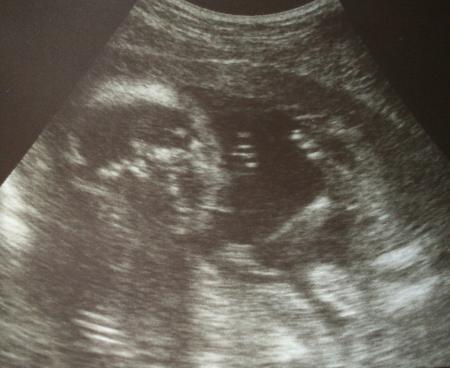

Bild

Eindeutig Junge!